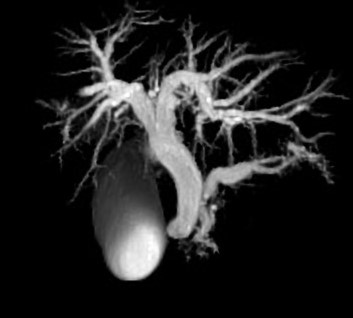

MRCP image confirms the absence of gallbladder and a normal biliary tree (Courtesy Dr. V. Penopoulos)